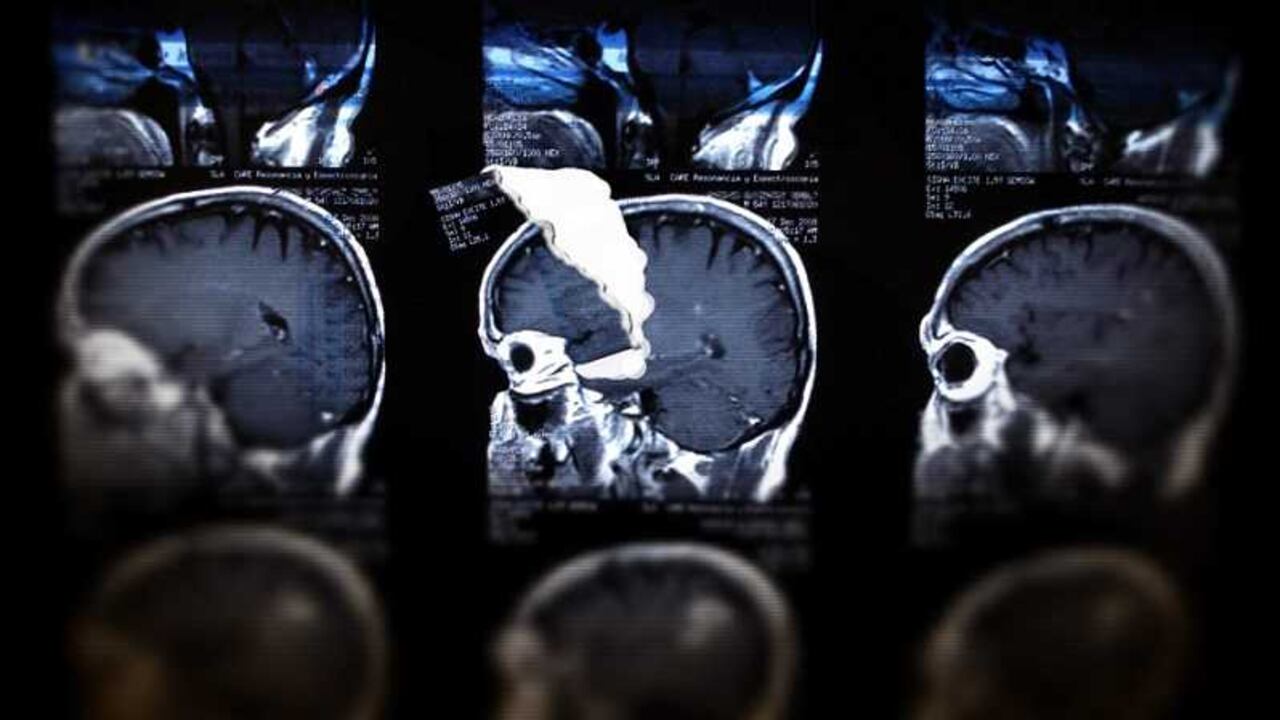

En este sentido, el laboratorio de investigación de neuroeconomía del Instituto Tecnológico de Massachusetts (MIT) ha incursionado en la investigación de la toma de decisiones al momento de hacer compras y ha sido consistente con la teoría neuroeconómica, pues hay evidencia que sugiere que circuitos neuronales anticipan las ganancias o las pérdidas, las preferencias sobre un producto u otro, mientras que precios relativamente altos activan la ínsula y desactivan la corteza prefrontal medial.

Es decir, desactivan el pensamiento superior y activan la parte del cerebro que se relaciona con las emociones primitivas como el miedo, la angustia, etc.